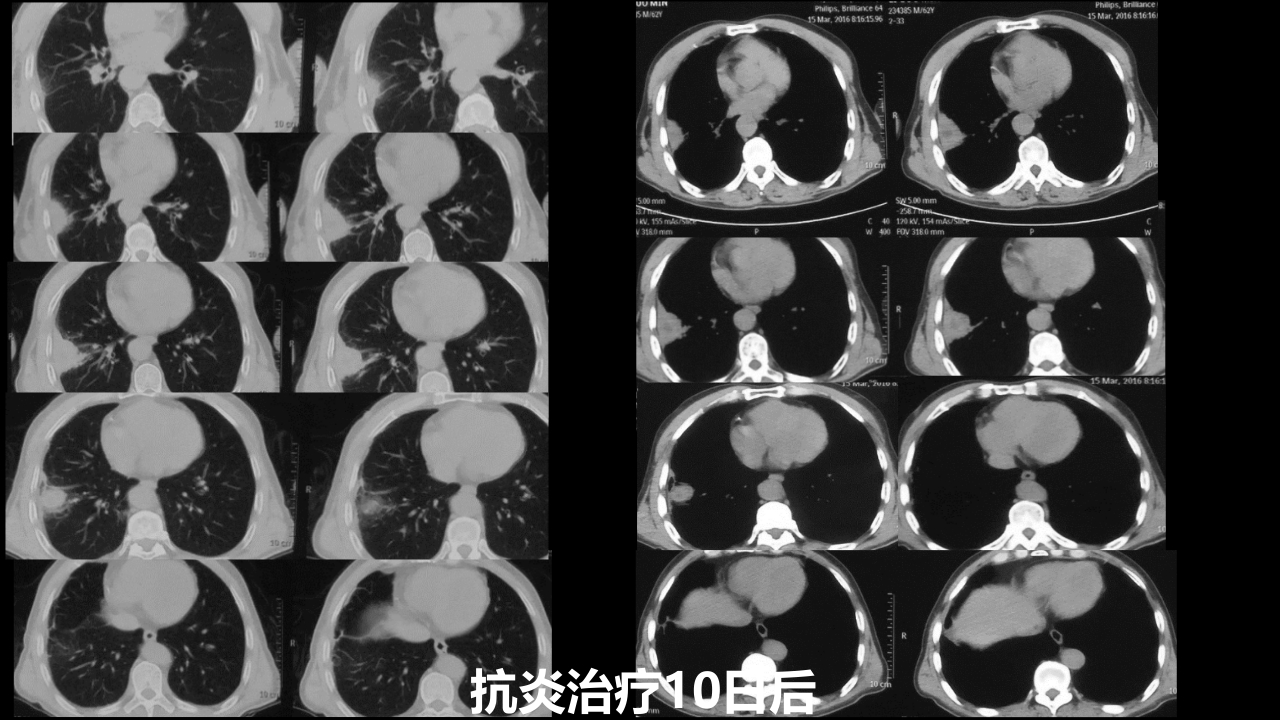

肺部肿块有效的影像检查选择